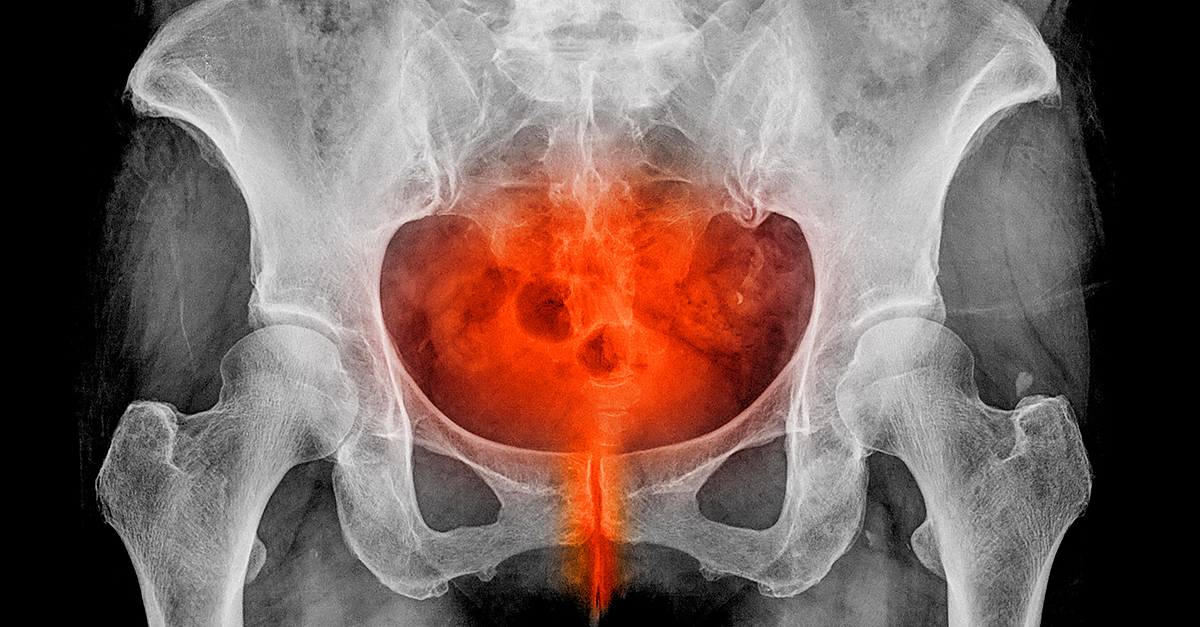

Greenleaf explores the biological gap in UTIs. The female reproductive system is more susceptible to them, while individuals born with penises are less vulnerable.

"Women have a shorter distance for the bacteria to get into the bladder. The rectum, vagina and urethra are very close together," she said. "It doesn't matter how clean a woman is, it is very easy for bacteria to pass back and forth. It has been quoted ranging from 14 to 30 times more likely than men. [In menopause], changes in vaginal pH and microbiome of the vagina from the drop in estrogen [mean] women lose the healthy bacteria that keep the 'bad guys' away."

"In my case, the recurrent UTIs were caused by pelvic organ prolapse (POP)," she said. "My bladder, cervix, uterus, anterior and posterior vaginal walls had all prolapsed. One of the first symptoms of POP is recurrent UTIs, dribbling after urinating or when you cough, sneeze or laugh. Younger women can also experience POP if they are weight-lifters, runners, have jobs where they are on their feet all day or are required to lift more than 50 pounds. If you've had children, especially with forceps or a fast vaginal delivery [or] women who unknowingly have connective tissue disorders, like myself, [we] are more prone to POP."